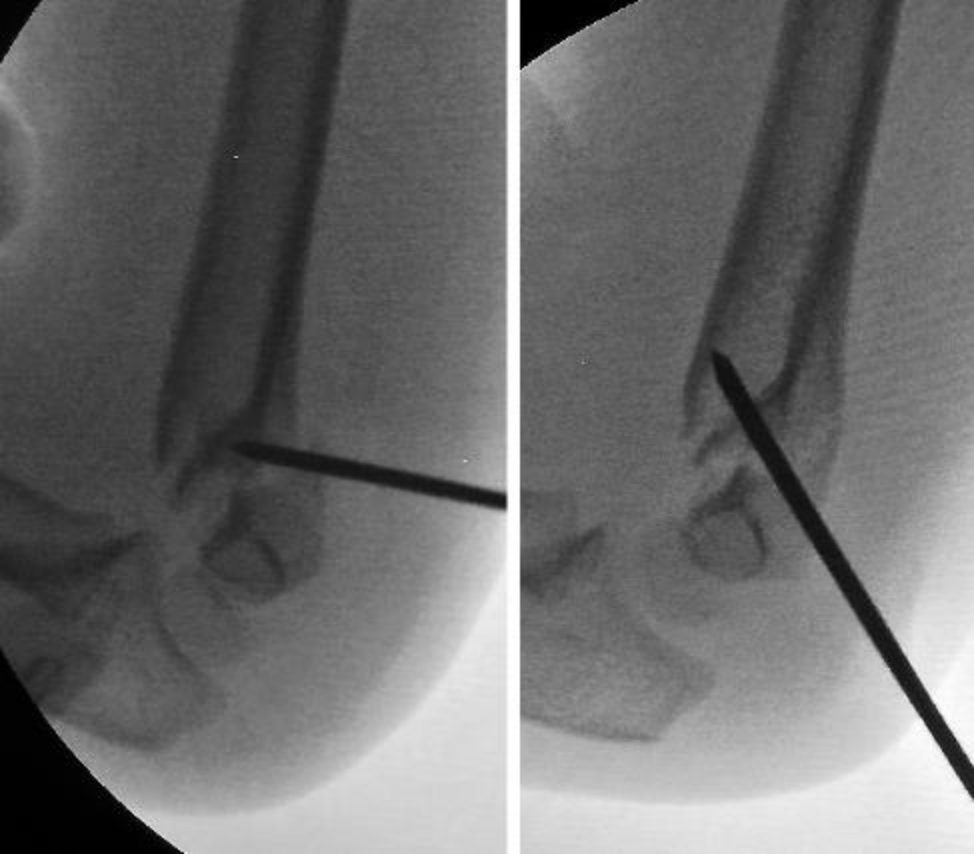

肱骨近端骨折的手术治疗指征见表1。骨折移位超过33% (Neer III或IV)或骨折成角超过40度的患者在达到骨骼成熟的2年内(男孩 14岁,女孩 12岁)可考虑复位。患者取仰卧位或改良沙滩椅位以进行正交成像(图1和图2)。随后,整个上肢被覆盖。在手臂内收的情况下,经皮插入2根2.0毫米的克氏针,并将其推进至骨折部位。在此位置,与手臂外展和旋转相比,更容易插入克氏针。在经皮放置克氏针时,必须避开腋神经。该神经位于肩峰前外侧6厘米范围内,而克氏针则放置在此位置远端。一旦克氏针的位置在x线片上得到确认,通过牵引、外展和旋转对骨折进行闭合复位。如果认为复位不充分,则使用2.5 mm Steinmann针辅助复位(Kapandji技术)。偶尔,骨膜或肱二头肌长头可能会在骨折部位造成干扰,这时需要通过三角肌胸肌入路进行切开复位。一旦复位成功,克氏针就会推进,随后移除Steinmann针。重要的是,要避免克氏针穿透关节面。随后,在连续透视下进行最大内旋和外旋测试,以评估稳定性和克氏针的最终位置。如果观察到骨折不稳定的迹象,则插入第三根2.0毫米的交叉钢针。然后剪断钢针,将其弯曲并留在皮肤外,以便在诊室内取出。

图1 A)初次就诊时的临床影像和X光片。B)闭合复位和经皮穿针术中的透视图像。C)3个月随访时的正位和侧位X光片。